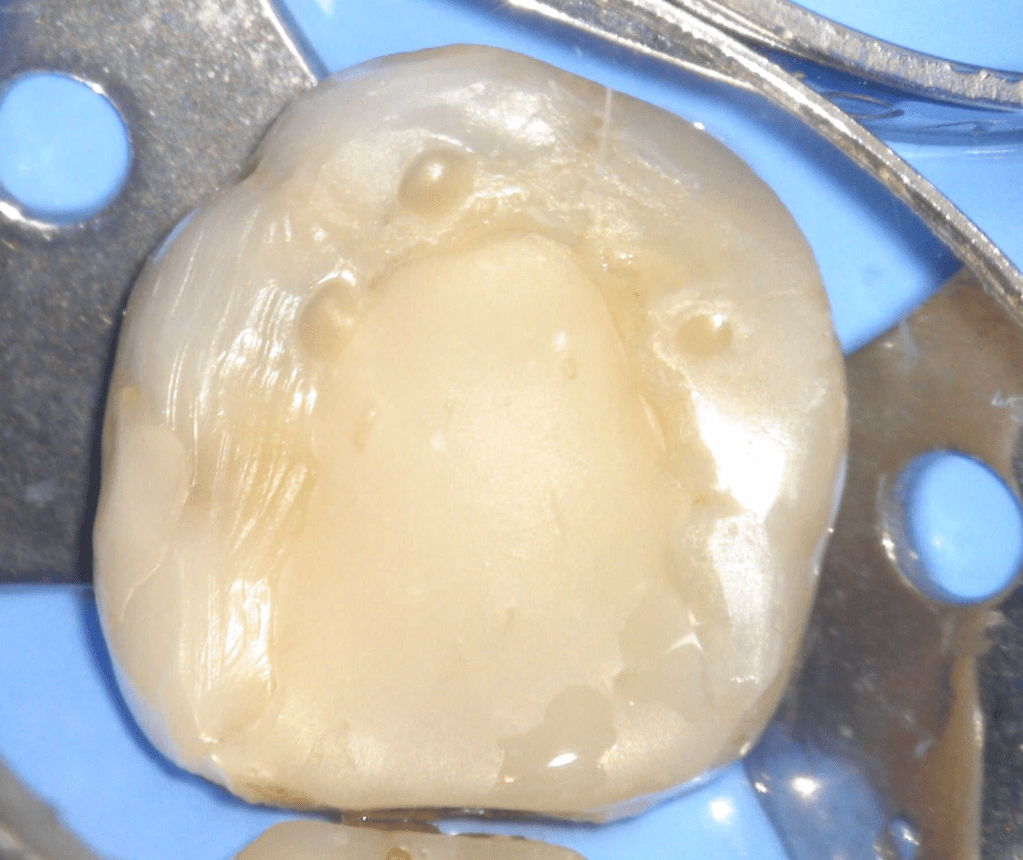

Fisura, remoción amalgama para explorar